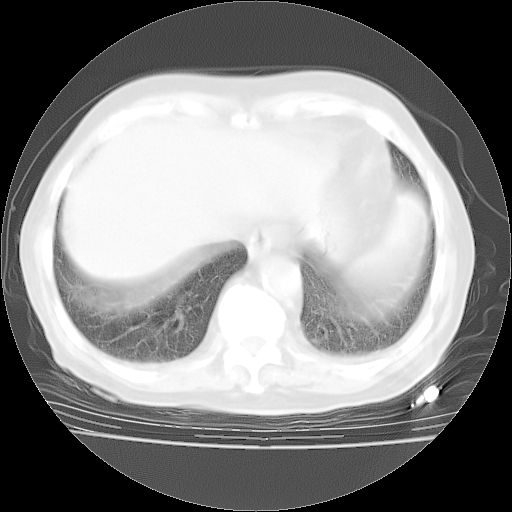

4月28日肺部CT——再次出现类似去年5月9日——透光度降低,“间质性”改变。